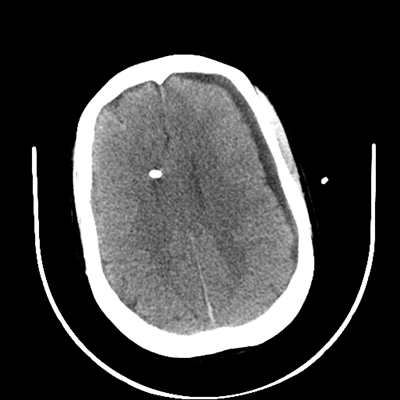

The patient goes down to CT. The following images are obtained. The subdural fluid collection is stable, as is the ventricular caliber.

NCHCT

Starting with the non-contrast head CT, we can appreciate that there's actually not much residual subarachnoid blood at all; it's essentially all resorbed already (and cleared through the EVD). The ventricular caliber is stable. With the CTA head (for convenience's sake, the MIPs were shown), it's subtle, but we can see that the PCAs on each side are not as smooth and regular. The right MCA, starting at the bifurcation, also becomes narrower. This is [radiographic] vasospasm. Now, looking at the CT perfusion-- specifically, the Tmax (MTT) map that were selected-- there's clearly some abnormality within the bilateral cerebellar hemispheres and occipital lobes. Not a lot, but it's there. Delving further into this map, we can appreciate that the areas of abnormality are mainly green, signifying that these areas have Tmax > 6 seconds. This is the threshold that is specific, not sensitive, for vasospasm.

Yes! It does. The patient had a decline in level of consciousness with diffuse loss of motor function. This does correlate to the basilar territory. (Alternatively, bilateral MCA vasospasm could also be responsible, reminding us that a decline in consciousness could technically be focal/multifocal.) Thus, we can say that this patient does have clinical vasospasm. Whether this will develop into irreversible DCI remains to be seen; at least, the non-contrast head CT and the other portions of the CT perfusion (not shown) currently don't [yet] suggest infarction.